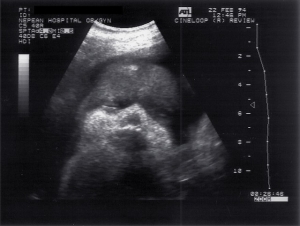

- Obstetrics 1973

Scans – Obstetric and General